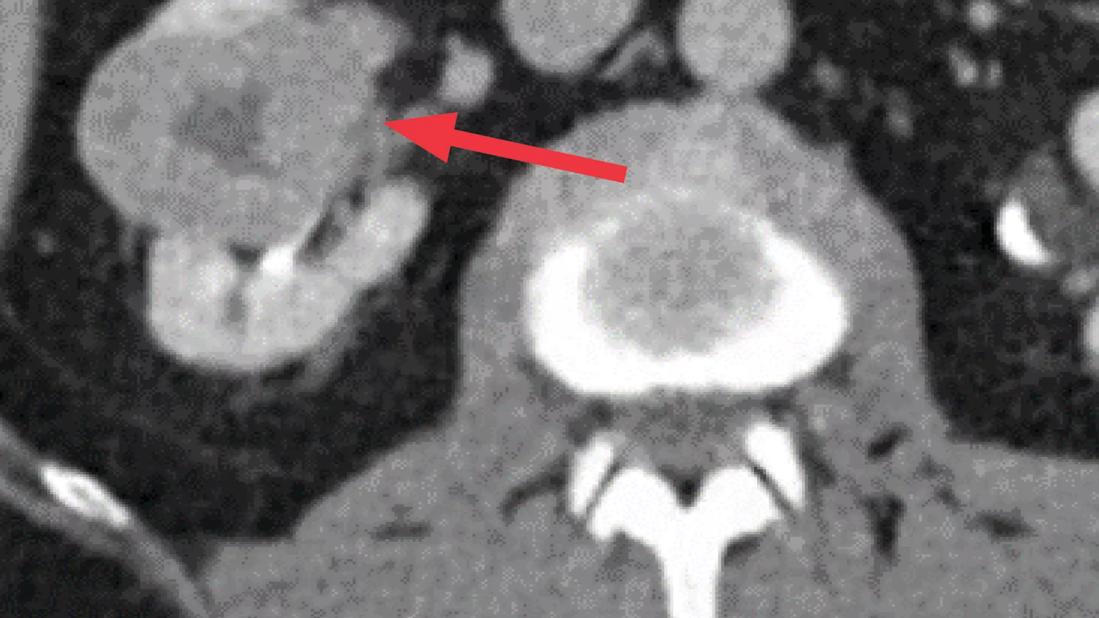

A 71-year-old male presented to Cleveland Clinic’s Department of Urology with a 4.9 cm hilar right renal mass. The tumor contour was somewhat irregular and the R.E.N.A.L. nephrometry score was 10. He had a history of coronary artery disease and a stent placed six years prior.

Based on imaging, the location of the tumor, near the hilum, would make a partial nephrectomy more technically challenging, and its irregular shape raised concerns for aggressive disease. The team considered the following:

Using computerized software to measure parenchymal volume based on imaging — an analysis that has largely replaced nuclear renal scans at our center — the team identified a baseline GFR of 83 and an SRF of 53% and 47% on the left and right, respectively. The RMB indicated a clear cell, grade 3 malignancy, suggesting that the tumor biology might be on the more aggressive end of the spectrum.

MIS radical nephrectomy confirmed that the malignancy was clear cell, pathological stage T3a (protruding into a branch vein), grade 4 with rhabdoid features, and all margins were negative. The patient’s post-operative GFR was 52, proximate to the team’s estimation of 55.

Though the tumor wasn’t large, it was — by all accounts — aggressive. The irregular contour on the imaging and RMB suggested increased oncologic potential. The SRF analysis revealed a normally functioning contralateral kidney, and an NBGFR estimation suggested it would maintain function following radical nephrectomy. In this case, Dr. Campbell explains, a partial nephrectomy could have put the patient at risk for more unfavorable outcomes.